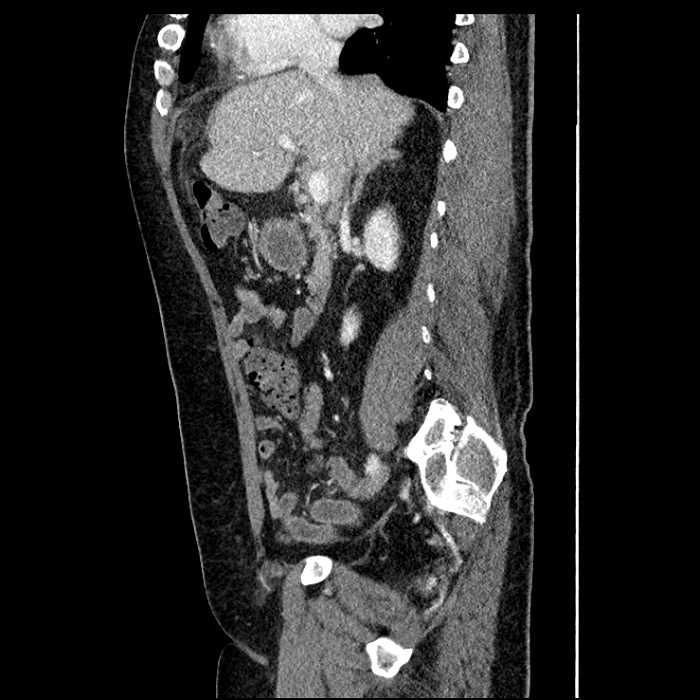

• Large fluid density structure in hepatic segments 7 and 8 measuring 10 x 7 x 7 cm with internal septation and circumferential ill-defined low density compatible with edema

• Peripherally enhancing subcapsular collections along the anterior margin of the left hepatic lobe measuring 3 x 1 cm and 2 x 1 cm

• Clearly marginated fluid density structure in segment 7 and several other scattered tiny hypodensities, which likely represent cysts

• Mild mural thickening of a segment of the sigmoid colon with adjacent fat stranding and a 1.5 cm fluid and gas collection along the tip of an inflamed diverticulum

• Loss of the normal fat plane between this collection and adjacent loops of small bowel, which demonstrate mural thickening

• High grade stenosis of the left common iliac artery, with the left internal and external iliac arteries remaining patent

Acute sigmoid diverticulitis complicated by a small contained perforation and a large abscess in the right hepatic lobe. Additional small subcapsular abscesses along the anterior margin of the left hepatic lobe.

Additionally, loss of the normal fat plane between the peridiverticular collection and adjacent thickened loops of small bowel raises the potential for an enterocolonic fistula.

High grade stenosis of the left common iliac artery. The left external and internal iliac arteries are patent.

Hepatic abscess showing the double target sign with low density internally surrounded by a thin inner enhancing rim (red arrow) and ill-defined outer low density rim (yellow arrow). Blue arrow indicates an internal septation. Red arrows: additional smaller subcapsular abscesses. Red arrow: focal contained perforation associated with diverticulitis.